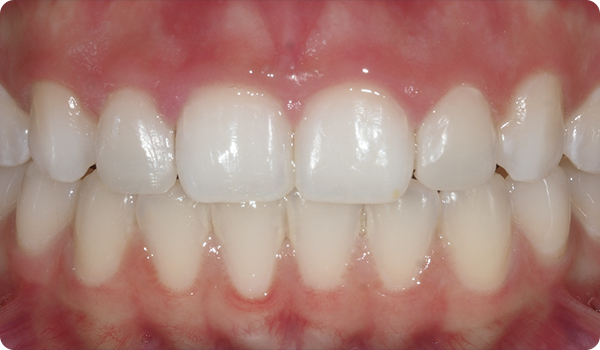

Sourires en place

Grâce à Right, vos patients obtiendront le sourire qu'ils souhaitent quand ils le souhaitent, de manière confortable et indétectable.

L'alignement des dents avec Right est la solution parfaite et la plus conservatrice pour les futurs traitements de blanchiment ou de facettes. Elle apportera la perfection au sourire du patient.